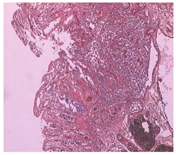

患者男性,47岁,因"持续性腹胀、腹痛3 d,症状加重伴黑便1 d"急诊入院,既往有痛风10余年,长期服用强的松、保泰松、布洛芬治疗,余无特殊病史。入院查体:体温38.5℃,脉搏110次/min,呼吸26次/min,血压90/65 mmHg(1 mmHg=0.133 kPa),意识清楚,稍烦躁,皮肤巩膜无黄染,双肺呼吸音粗,全腹稍膨隆,上腹部压痛明显,轻度肌紧张,肠鸣音1~2次/min。实验室检查:白细胞2.85×109/L,血小板30×109/L,谷丙转氨酶115 U/L,谷草转氨酶419 U/L,血尿素氮16.8 mmol/L,肌酐439 μmol/L,Ca2+ 1.65 mmol/L,淀粉酶2 790 U/L,血糖12.8 mmol/L,降钙素原80.91 μg/L,脑钠肽9 719 pg/ml。入院诊断为急性胰腺炎、休克代偿期、MODS、痛风。积极采取禁食、胃肠减压、解痉镇痛、抑制胰液分泌、补液扩容、营养支持和中药等综合治疗措施,病情无缓解,腹痛、腹胀进一步加重。入院后10 h腹部增强CT报告:小肠不全性梗阻,左中上腹小肠肠壁下积气,肠坏死可能;右中下腹小肠肠壁异常强化,考虑炎性病变;腹腔积液;胰体、尾部强化不均匀伴周围积液,双侧胸腔积液(图1)。诊断性腹腔穿刺抽出暗红色血性液体,考虑SAP合并肠坏死可能。征得家属同意,急诊剖腹探查,术中发现约有100 cm的末端回肠坏死和右半结肠坏死,胰体、尾部坏死。行末端回肠切除术+右半结肠切除术+胰体尾坏死组织清除胰周引流术+回肠造瘘术。术后转ICU进一步治疗,因病情重,术后第3天因多器官功能衰竭死亡。术后病理示肠壁细胞坏死,大量炎性细胞浸润(图2)。